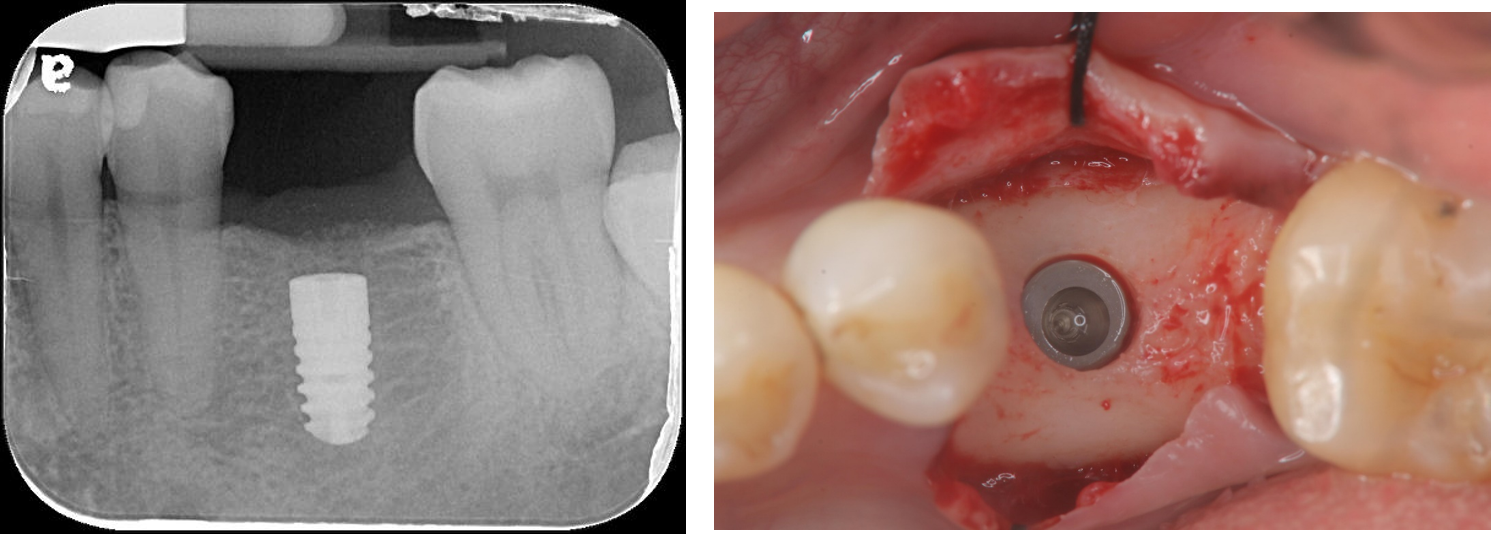

下顎植牙

上顎植牙二階手術